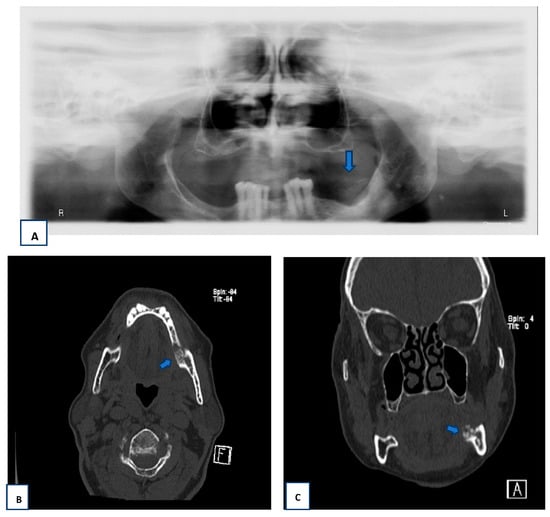

2.2. Radiographic Findings